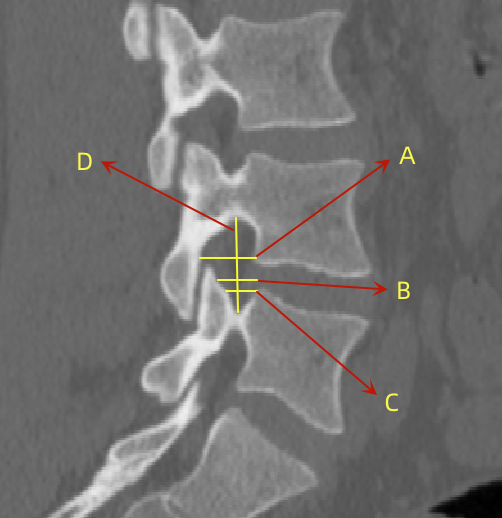

2、通過術前CT測量L4-5節段手術部位的(1)上位椎體后下角水平方向到關節突關節的距離(A);(2)纖維環后緣的中點水平方向到關節突關節的距離(B);(3)下位椎體后上角水平到關節突的距離(C);(4)上位椎體的椎弓下切跡與下位椎體椎弓上切跡連線的距離(D),圖 6;(5)在手術節段的棘突矢狀位CT層測量椎間隙高度(E),圖 7;(6)在手術節段的關節突關節橫截面CT層測量關節突間距離(F),圖 8,再通過術中及術后CT判斷患者椎間孔成型級別,將A-F測量數據與5級成型中的各級別成型進行相關性分析。

圖 6 A-D的測量方式 |